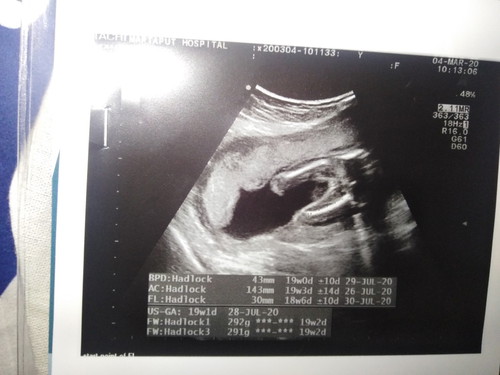

ช่วยดูหน่อยค่ะ น้องชายหรือหญิง ????

คล้ายๆกันเลยน่าจะหญิง ของเราหมอบอกหญิง

ยินดีด้วยน่ะค่ะคุนแม่. คุนได้ลูกสาวจ้า

น้าจะหญิงนะคะ แม่บ้านนี้ผชเหนชัดมาก

หญิงจ้า ถ้าผุชายจะเห็นชัดมาก

กรกฎา เหมือนกันจ้า หญิงจ้า